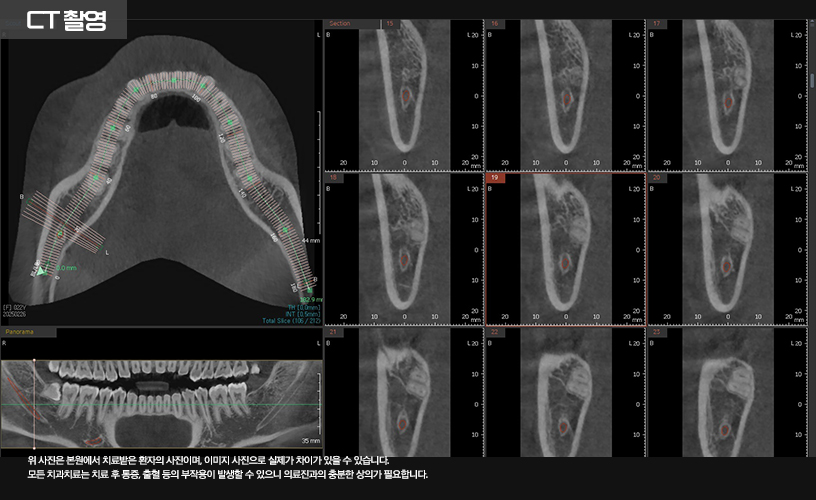

발치 전 3D CT 촬영을 통해

사랑니와 하치조 신경의 위치를

정확히 파악하는 것이 필수적입니다.

CT 촬영을 통해 신경관과 사랑니의 위치를

파악한 다음 발치가 이루어졌습니다.